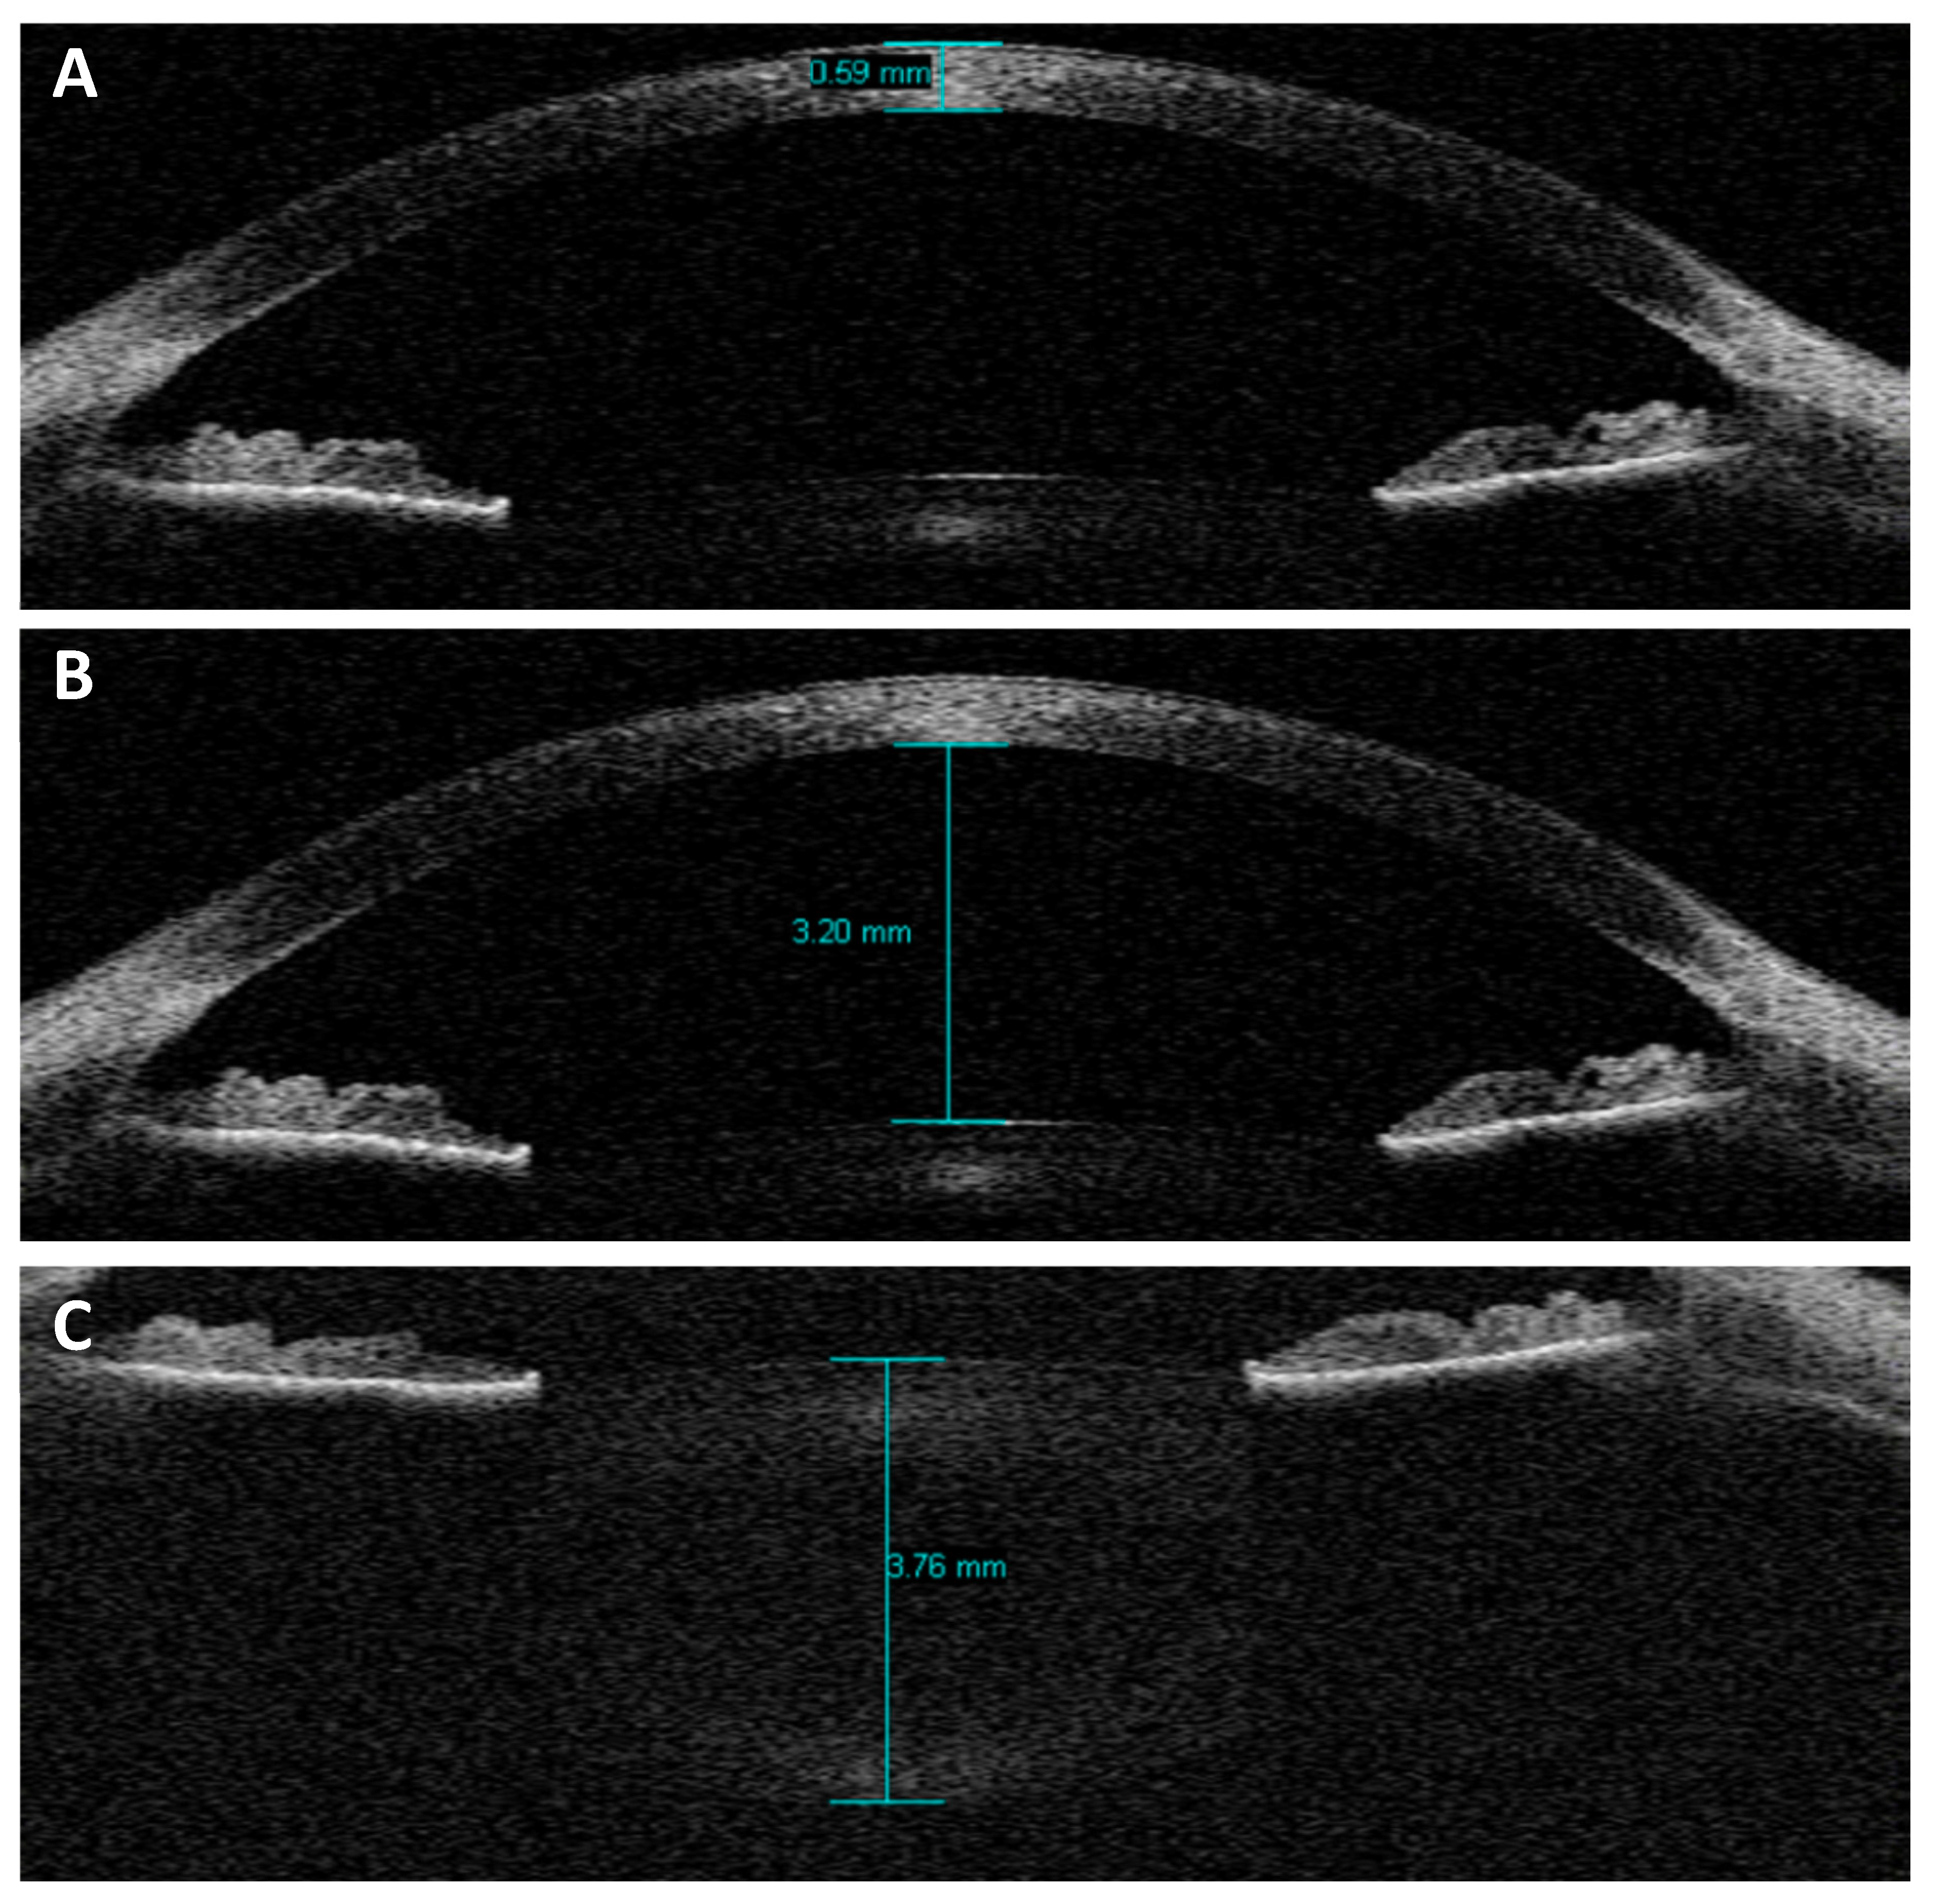

2. Materials and Methods

3. Results